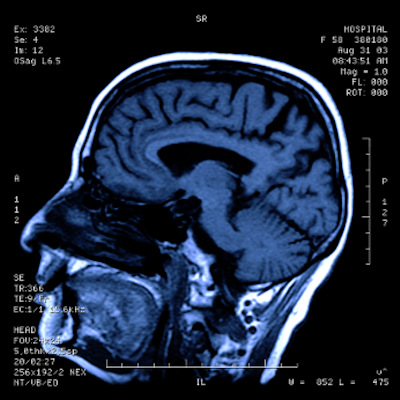

Over a period of 24 months, researchers in the CoverScan study will gather detailed multiparametric MRI and genetic studies to determine the prevalence and degree of lung, heart, kidney, liver, pancreas, and spleen injury in a cohort of over 500 patients recovering from the COVID-19 respiratory disease following infection by the SARS-CoV-2 virus. The CoverScan study also will assess changes in the health of multiple organs and whether genetic traits influence recovery.